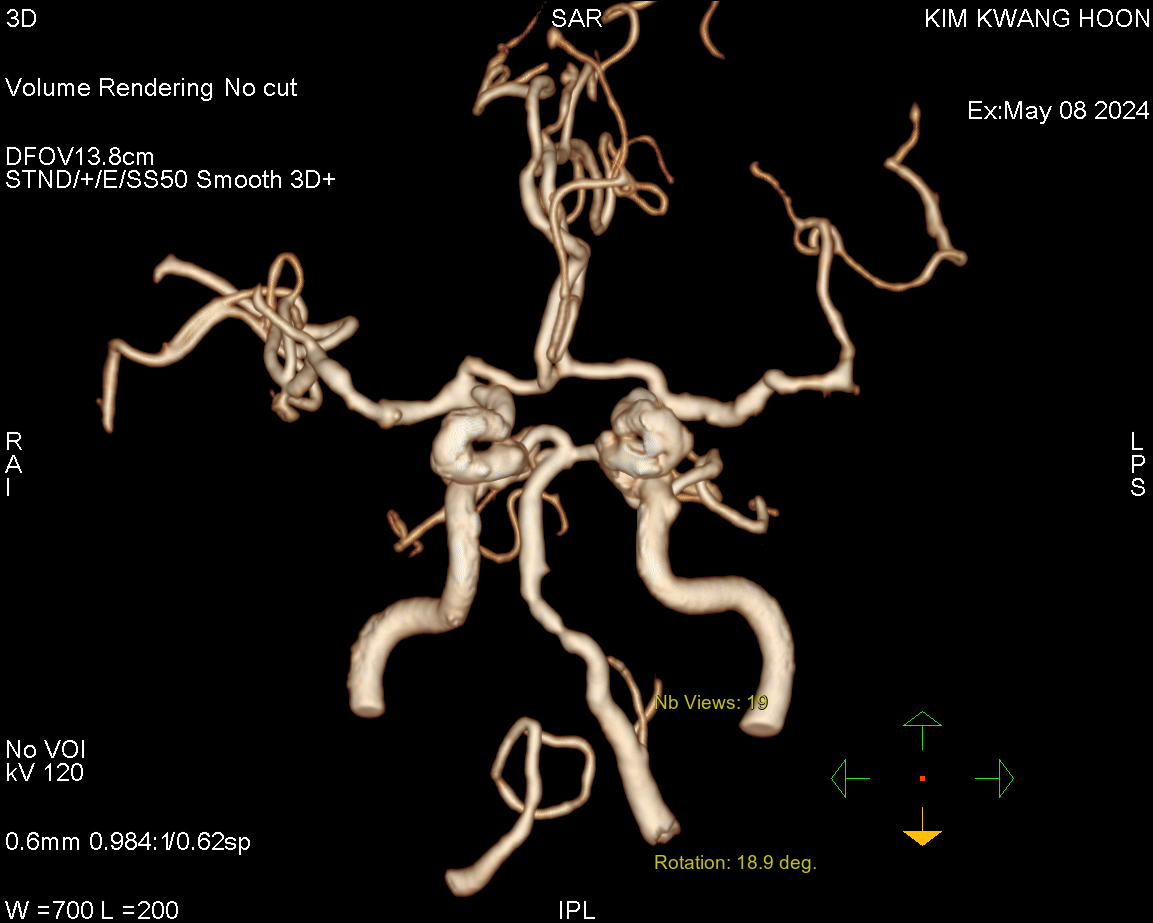

때문에 바로 brain CT angio + perfusion 검사를 통해 뇌동맥의 막힌 부분을 찾고, 그 부분을 뚫어줄 경우 살아날만한 경계에 있는 뇌조직을 확인하기로 하였다.

예상대로 환자의 뇌동맥 중 좌측 중뇌동맥의 분지인 M2의 inferior division이 막혀 있는 상태로 확인되었다.

또한 perfusion CT 영상에서도 좌뇌 MCA 영역의 앞쪽 일부분은 경우에 따라 기능 보전이 가능해 보이는 영역이 있었다.